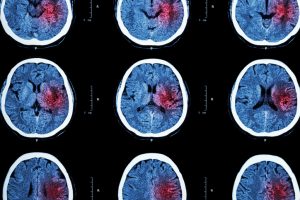

Stroke can be deadly, and the risk of stroke is particularly high among elderly patients. However, stroke can actually affect patients of any age—including newborns. Because stroke is perceived as being a problem for older patients, younger individuals who suffer stroke may be misdiagnosed. These serious emergency room errors may be a form of medical malpractice if the physician deviated from standard diagnostic procedures.

When stroke occurs, every second counts. The misdiagnosis of stroke may mean that a patient cannot receive clot-busting drugs within a critical time period to improve the chances of survival. When misdiagnosed patients do survive a stroke, they may suffer serious, lifelong consequences as a result of the death of brain cells.